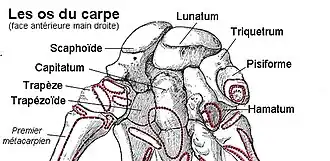

L’os hamatum (ou os crochu) est l'os le plus médial de la deuxième rangée du carpe.

L'hamatum est un os irrégulier à six faces présentant une excroissance osseuse antérieure : l'hamulus de l'os hamatum.

La face supérieure étroite, convexe et lisse s'articule avec le lunatum.

La face inférieure présente deux facettes articulaires concaves séparées par une crête osseuse. Ces facettes s'articule avec les quatrième et cinquième métacarpiens.

La face postérieure est triangulaire et rugueuse et reçoit des insertions ligamentaires.

La face antérieure présente en bas et médialement l'hamulus.

La face latérale s'articule dans sa partie supérieure et postérieure avec le capitatum, la partie restante est rugueuse pour des attaches ligamentaires.

La face médiale présente une surface articulaire avec le triquétrum.